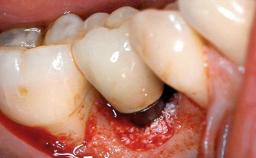

A 24-year-old female patient was treated with an implant- supported crown for single-tooth replacement at site 11. A Straumann Bone Level RC implant (Institut Straumann AG, Basel, Switzerland) was placed with simultaneous bone augmentation, and the periimplant emergence profile was conditioned with a fixed implant-supported provisional crown. After finalization of the mucosal architecture, the clinical situation was transferred by means of a custom impression post for fabrication of an implant-supported screw-retained onepiece crown consisting of a CARES® zirconia abutment (Straumann) with a direct ceramic veneer.